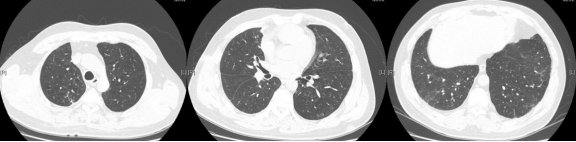

病例:男性,33岁,劳力性呼吸困难4年,加重3月,在治疗之前,我们看到的影像有些磨玻璃影、马赛克征,还有小叶中央型结节,并进行了外科肺活检。患者在从事铸造工作过程中间断接触异氰酸酯。停止工作暴露,并糖皮质激素经过治疗后,病情好转,但停用激素后又出现了肺部弥漫的磨玻璃影,肺功能也有所下降。

图:(从左至右)治疗前、脱离暴露+激素治疗10月、停激素18月